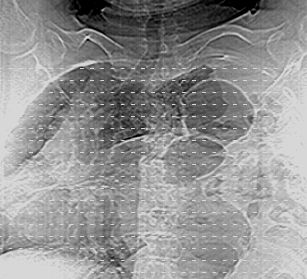

标题: CT10753:女, 64岁 隔疝 [打印本页]

标题: CT10753:女, 64岁 隔疝

女, 64岁 三十年前胸部外伤史, 间断胸闷,

典型左侧膈疝,疝出物为胃和大网膜,纵隔右移

同意左侧膈疝,不过,有过外伤史,左肺有受压征象,同时有胸膜增厚。

左侧隔疝(创伤性?),与外伤关系大。